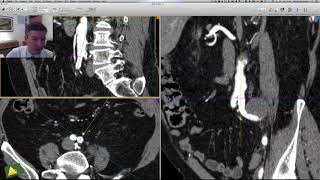

Reconstrução 3D no OsiriX: Volume Rendering básico, Crop, Presets e remoção de ossos.

Inscreva-se no Canal Ver Todas as AulasReconstrução 3D no OsiriX: Volume Rendering básico, Crop, Presets e remoção de ossos.